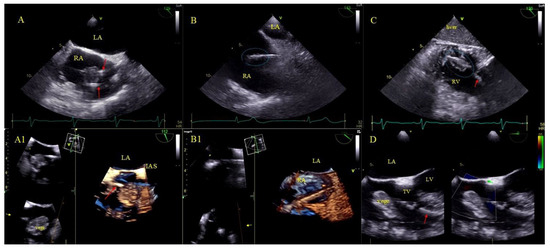

2.5. Echocardiographic Findings Associated with Endocardial Leads: Definition and Classification According to the Anatomy and Characteristic Features